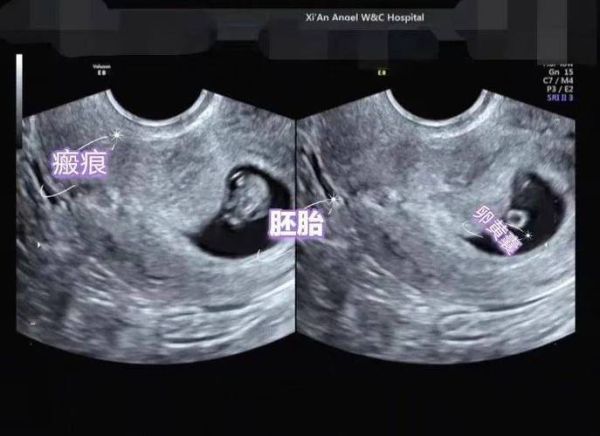

**经阴道超声** - 探头直接进入阴道,贴近子宫,图像清晰,**无需憋尿也无需空腹**。 - 适合孕周较早(<10周)或腹部脂肪较厚的孕妇。 **经腹部超声** - 探头隔着腹壁扫描,需要**膀胱作为“声窗”**把子宫顶起,图像才清楚。 - 检查前1小时喝500–800 ml水,有明显尿意即可,**不必空腹**。 - 若既想憋尿又怕呕吐,可少量进食清淡饼干,避免胃里完全空荡引发低血糖。 ---孕中晚期B超:什么情况下需要空腹?

- 5–8周:确认宫内孕,可选经阴道或经腹。经腹需憋尿,无需空腹。